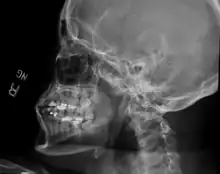

As with other joint dislocations, clinical history and examination are important for diagnosis. Commonly, plain and panoramic X-rays are used to determine the relative position of the mandibular condyle. If a complex or unusual injury is suspected, computed tomography is most reliable in diagnosing dislocation and possibly associated fractures or soft tissue injuries.

Bilateral anterior dislocation of the jaw -

Jaw dislocation following relocation -